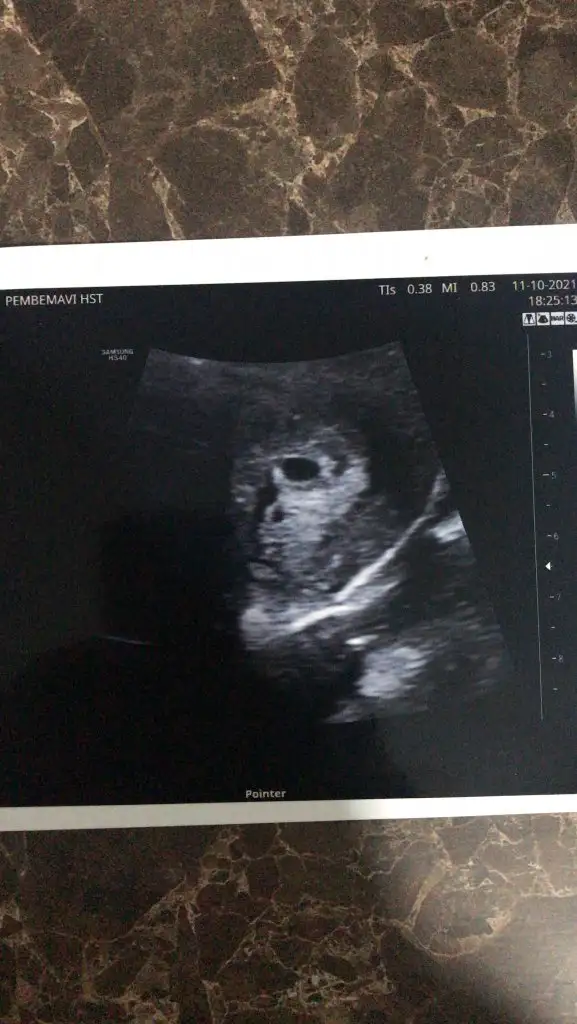

Ay hadi senin de gözün aydın olsun canımEvet benim aklıma watsap da geldi de kimse kimseyi tanımıyor anne adaylarıyla daha samimi fikir paylaşımı isterdim. Geldik doktordan bugüne aldım randevuyu dayanamadım. Kalp atışı duyulmadı diye vajinal baktı doktor duyduk sonunda. Şükürler olsun 6+2 gibi dedi doktor. Korktum birden duymayınca ya

tahmini doğum tarihi : 07.06.2022

ilk çocuk

keseyi 5+0 da gördüm 4+0 da olabilir ondan tam emin değilim doktor net bir şey söylemedi. sadece 1 hafta gerisin geç döllenme olmuş dedi. son bat tarihim 31 ağustostu. ordan hesaplarsam 6 hafta olması lazım aslında ama 1 hafta geri diyince 5 haftaya denk geliyor sanırım :)